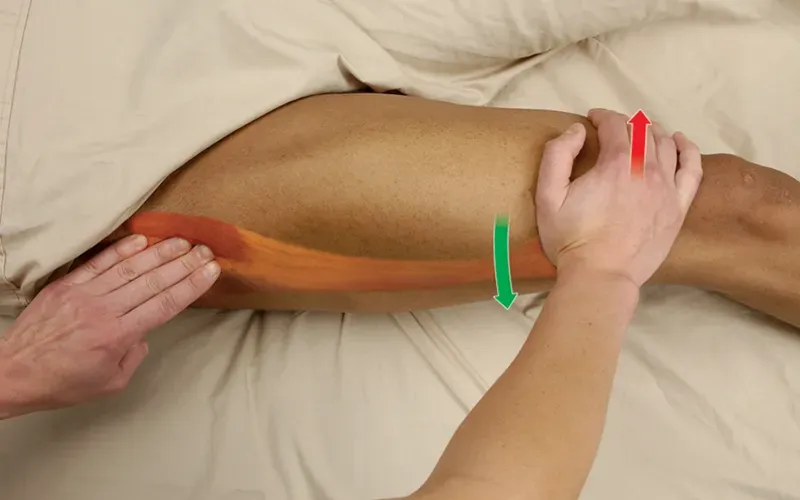

Tightness in the TFL, gluteus maximus, and associated iliotibial band can create friction proximally on the greater trochanter or distally on the lateral condyle of the femur. This excessive friction often results in injury to the bursa or tendon. Maintaining optimal flexibility in the iliotibial band and strength balance between the adductors, abductors, and rotators of the hip helps prevent this problem. Poor fascial mobility and excessive tension may also play an indirect role in dysfunctional patellar tracking and the associated chronic knee pathologies.

Positioning: client supine with hip internally rotated.